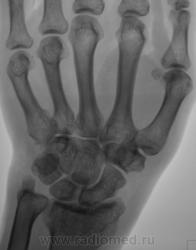

Пол пациента: Женский пол Тип патологии: Другое Область исследования: Скелетно-мышечная система Методы исследования: Rg Пациент с диагнозом "ревматоидный артрит" направлен на рентгенографию кистей. https://radiomed.ru/sites/default/files/styles/case_slider_image/public/user/12/2.pb100037a.jpg?itok=yFjpd1IX https://radiomed.ru/sites/default/files/styles/case_slider_image/public/user/12/3.pb100038.jpg?itok=92itQ56R https://radiomed.ru/sites/default/files/styles/case_slider_image/public/user/12/4.pb100038a.jpg?itok=rsA7mSo8 ID:8677 Чт, 11/11/2010 - 01:03 #1 Makcimalist Не на сайте Был на сайте: 11 лет 8 месяцев назад Зарегистрирован: 08.05.2010 - 14:28 Публикации: 1994 - специфич. признаков начальных стадий РА не нашёл... -------------- "Просто, по видимости, не видеть логики в очевидных вещах - это тоже одно из свойств некоторых умов, наряду с грустными думами о свойствах ума других." © Vega 08/10/2011 Чт, 11/11/2010 - 14:44 #2 Катенёв Валенти... Не на сайте Был на сайте: 7 лет 2 недели назад Зарегистрирован: 22.03.2008 - 22:15 Публикации: 54876 Норму писать? Сб, 13/11/2010 - 01:28 #3 Makcimalist Не на сайте Был на сайте: 11 лет 8 месяцев назад Зарегистрирован: 08.05.2010 - 14:28 Публикации: 1994 Начальные проявления остеоартроза пястно-фаланговых,м/фаланговых суставов... (Норма бывает п/е рождения... и то не всегда...) -------------- "Просто, по видимости, не видеть логики в очевидных вещах - это тоже одно из свойств некоторых умов, наряду с грустными думами о свойствах ума других." © Vega 08/10/2011 Сб, 13/11/2010 - 19:53 #4 Глазков Игорь А... Не на сайте Был на сайте: 9 месяцев 2 недели назад Зарегистрирован: 19.12.2008 - 20:41 Публикации: 1597 Имеются кистовидные просветления костной ткани в эпифизах костей. Прийди к Себе

- специфич. признаков начальных стадий РА не нашёл...

Начальные проявления остеоартроза пястно-фаланговых,м/фаланговых суставов...

Имеются кистовидные просветления костной ткани в эпифизах костей.